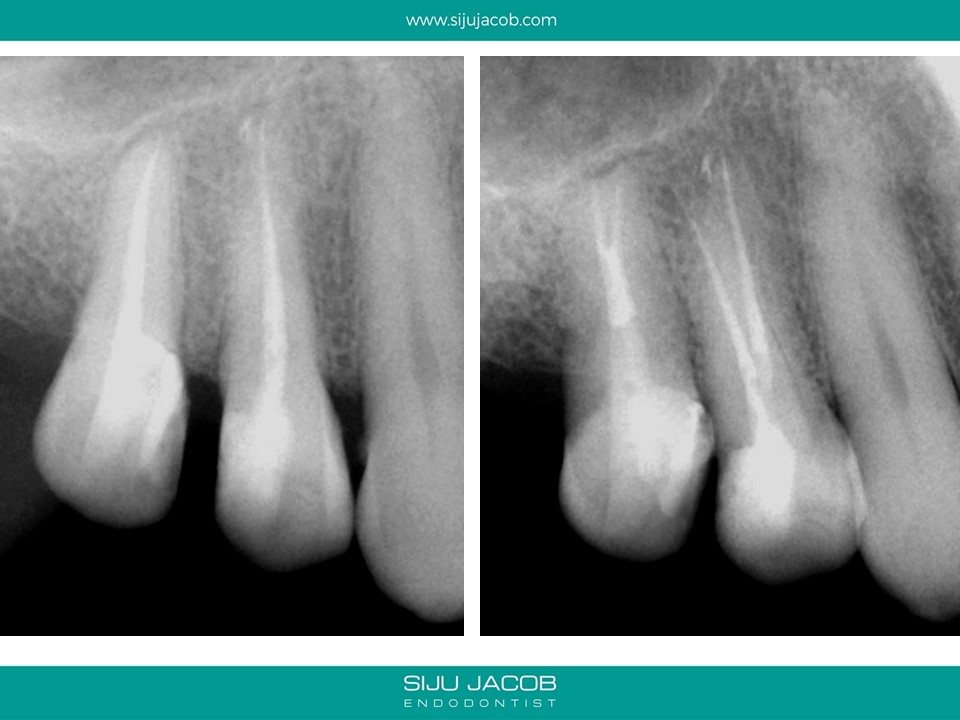

This maxillary premolar bufurcated quite deep into two canals. These type of cases are good examples of anatomy that can easily be missed without magnification.